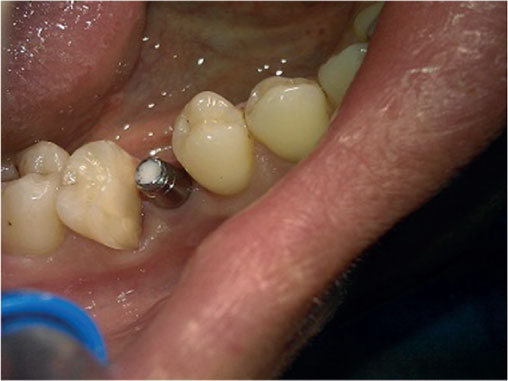

Photo 4. Oral cavity of the same patient: state of alveolar process, dentition and mucous membrane in the area of mandibular dentition defect.